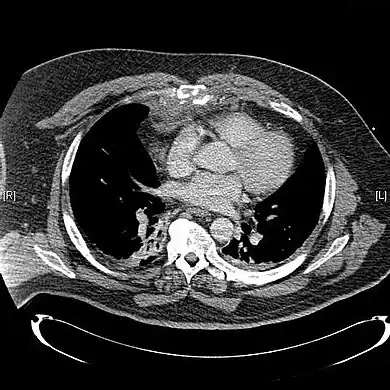

X-rays of the chest are taken in people with chest trauma and symptoms of sternal fractures, and these may be followed by CT scanning.[12] Since X-rays taken from the front may miss the injury, they are taken from the side as well.[13]